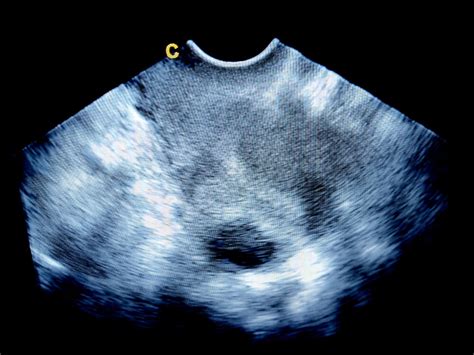

Pri rednih ultrazvočnih pregledih zdravnik ocenjuje tudi razvoj prsnega koša in gibanje plodovih dihalnih mišic. V določenih primerih, kot so prirojene nepravilnosti trebušne prepone ali malformacije pljuč, je potrebno dodatno spremljanje z naprednimi diagnostičnimi metodami.

Zdravstveni delavec pogosto diagnosticira pljučno hipoplazijo z rutinskim ultrazvokom med nosečnostjo. Za potrditev lahko izvedejo nadaljnji MRI (magnetnoresonančno slikanje).

Včasih zdravstveni delavec diagnosticira pljučno hipoplazijo ob rojstvu ali kmalu po njem. Če ima vaš dojenček težave z dihanjem, bo zdravnik z rentgenskim slikanjem prsnega koša iskal pljučno hipoplazijo in druge pljučne bolezni.

Intrauterina rastna omejitev (IUGR) med nosečnostjo morda ne kaže vedno očitnih simptomov. Ultrazvok je glavno orodje za ocenjevanje rasti in razvoja ploda. Če sumite na IUGR, se za oceno obrnite na svojega zdravstvenega delavca.